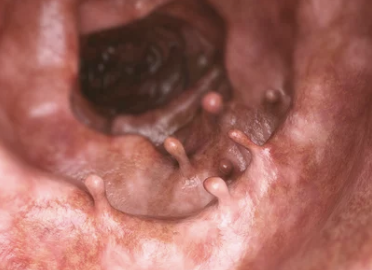

대장내시경은 대장과 직장의 내부를 검사하는 의료 절차입니다. 이 검사는 대장의 내부를 직접 보기 위해 유연한 관과 카메라가 달린 장치인 내시경을 사용합니다. 대장내시경은 다양한 목적으로 사용되며, 주로 다음과 같은 경우에 시행됩니다:

- 폴립 제거: 대장내시경 중에 발견된 폴립은 즉시 제거할 수 있으며, 이 폴립은 암으로 발전할 가능성이 있는 조직입니다.